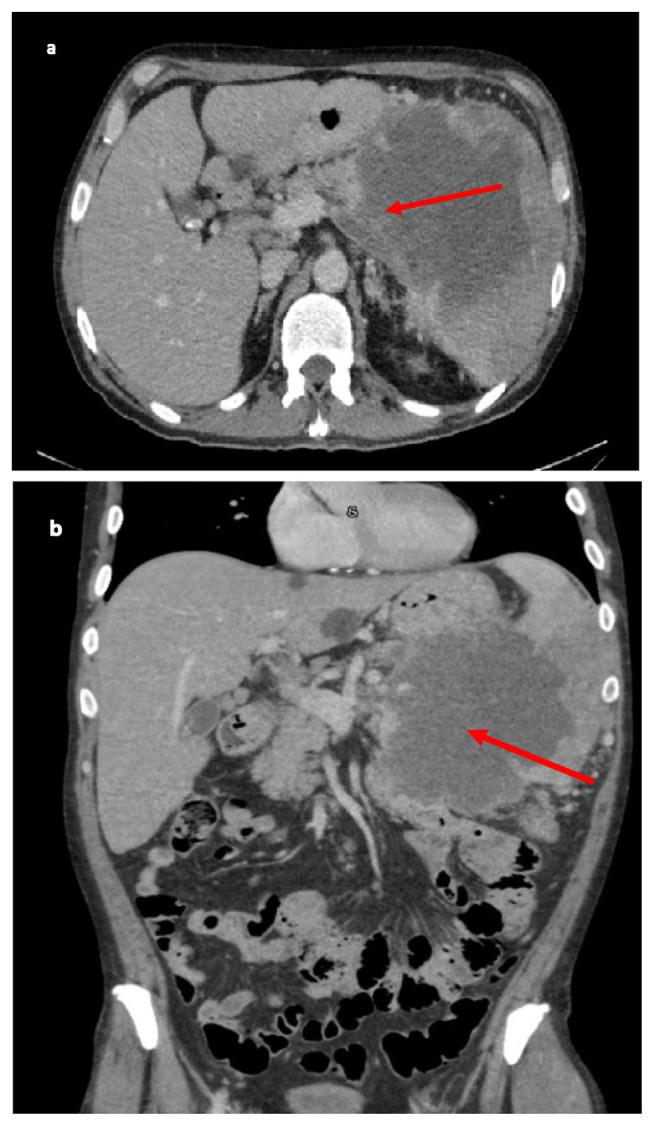

One-half of patients with newly diagnosed pancreatic cancer will have metastatic disease at the time of diagnosis, mainly due to its non-specific initial clinical presentation which includes abdominal pain, dyspepsia, weight loss, bowel habit changes, jaundice and pruritus. The signs, symptoms and stage of the disease at initial diagnosis depends on the origin of the primary tumor, with tumors of the head presenting earlier with obstructive symptoms while tumors of the body/tail are often diagnosed at an advanced stage due to their non-specific presentation. The most common sites of metastasis are the lymph nodes, liver, lung, and peritoneum. The presence of metastatic disease in the skeletal muscles is a rare manifestation of pancreatic cancer and has been described in a limited number of cases. We report the case of a pancreatic cancer patient with a solitary muscle lesion as the only site of extra-nodal metastasis upon initial presentation.

新诊断的胰腺癌患者中有一半在诊断时就已出现转移性疾病,主要原因是其最初的临床表现不具有特异性,包括腹痛、消化不良、体重减轻、排便习惯改变、黄疸和瘙痒。疾病初诊时的体征、症状和分期取决于原发肿瘤的起源部位,胰头肿瘤较早出现梗阻性症状,而胰体/胰尾肿瘤由于表现不具特异性,往往在晚期才被诊断出来。最常见的转移部位是淋巴结、肝脏、肺和腹膜。骨骼肌出现转移性疾病是胰腺癌的一种罕见表现,仅有少数病例有过相关描述。我们报告了一例胰腺癌患者,其最初表现为孤立性肌肉病变,是结外转移的唯一部位。